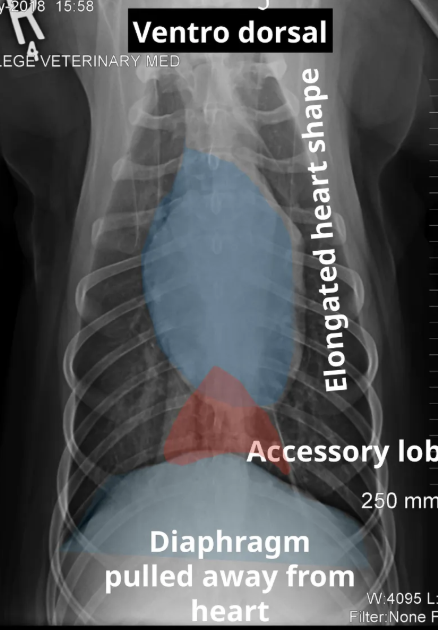

characteristics of DV view

A

• reverse D shape of the heart

• diaphragm touching the cardiac shadow

characteristics of VD view

• elongated heart shape